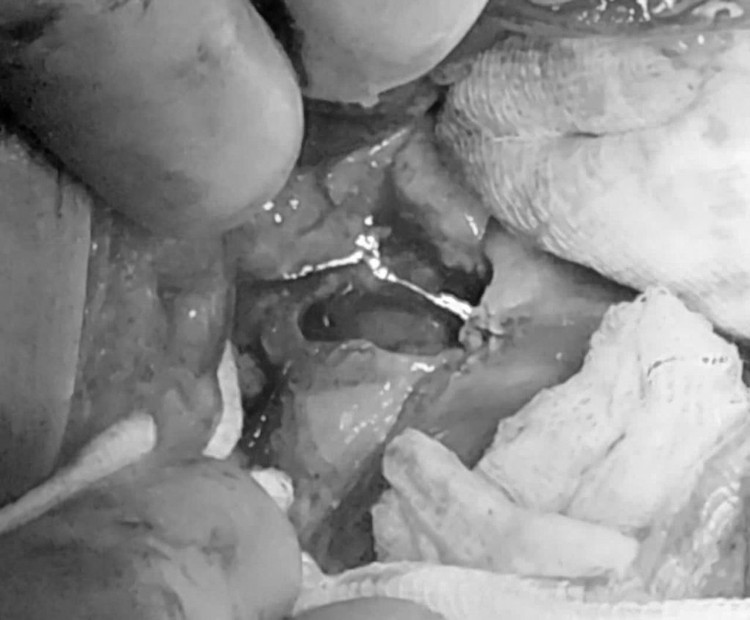

![]() |

| Thăm khám cho bệnh nhân sau phẫu thuật - Ảnh BVCC |